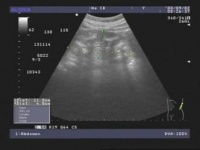

海绵肾的声像图特征:肾锥体内呈分布一致的高回声区,呈放射状排列,这是集合管囊腔较小,形成大量的反射界面,内部可有成簇的小结石形成(在乳头区呈放射状排列),所以呈高回声,而没有无回声区的囊腔显示。肾皮质回声均匀,肾脏大小接近正常。

海绵肾的诊断与鉴别诊断:在肾脏内可见肾锥体呈一致的高回声区,放射状排列,无囊腔回声显示,此为诊断本病的依据。本病需与肾乳头坏死多囊肾相鉴别,肾乳头坏死极为少见,且声像图上无高回声区呈放射状排列的肾锥体,容易鉴别